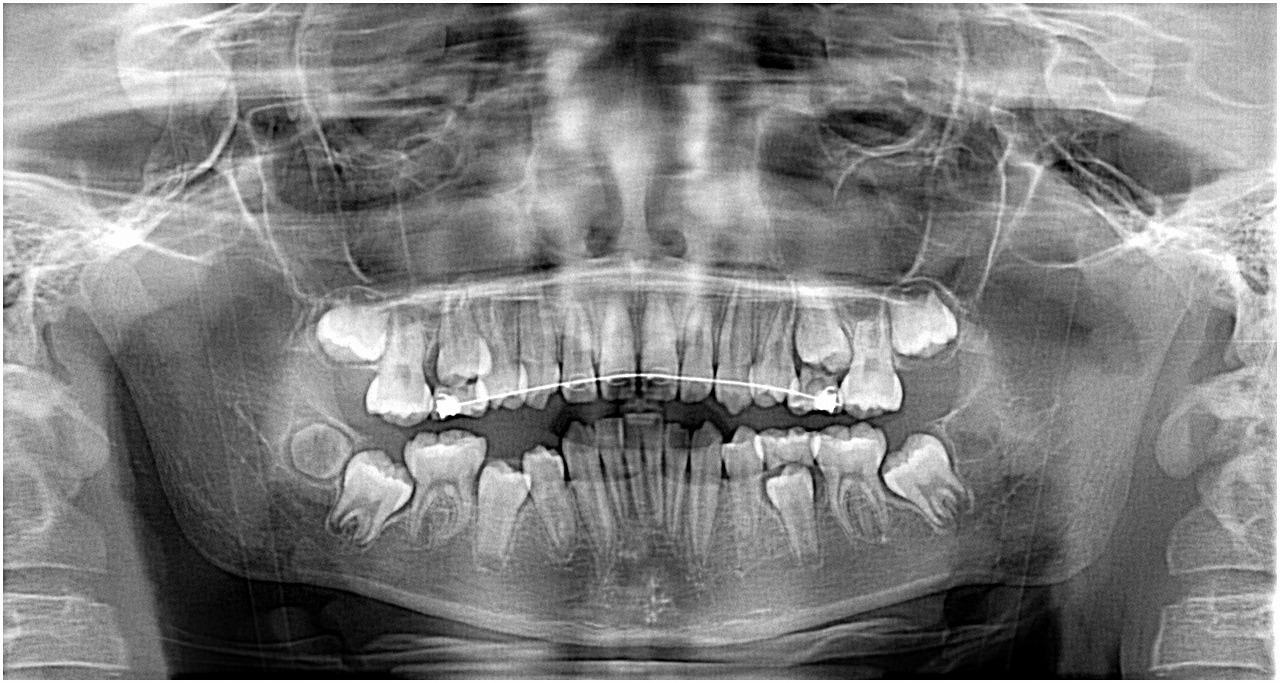

右下7番の萌出困難。矯正より抜歯依頼。 抜歯後に7に牽引用のボタン、ワイヤーをだしていたのですが、何もしなくとも自然萌出してきました。萌出時期の早い段階でよかったと思います。| |広島市安佐南区の歯科医院 右下7番の萌出困難。矯正より抜歯依頼。 抜歯後に7に牽引用のボタン、ワイヤーをだしていたのですが、何もしなくとも自然萌出してきました。萌出時期の早い段階でよかったと思います。 トップ お知らせ・ブログ 右下7番の萌出困難。矯正より抜歯依頼。 抜歯後に7に牽引用のボタン、ワイヤーをだしていたのですが、何もしなくとも自然萌出してきました。萌出時期の早い段階でよかったと思います。 右下7番の萌出困難。矯正より抜歯依頼。 抜歯後に7に牽引用のボタン、ワイヤーをだしていたのですが、何もしなくとも自然萌出してきました。萌出時期の早い段階でよかったと思います。 Web診療予約 初めての方へ 選ばれ続ける理由 院内設備について 歯が痛いしみる一般歯科 歯がぐらぐらする歯周病 健康な歯を保ちたい予防歯科 子供の虫歯予防をしたい小児歯科 銀歯をセラミックに審美歯科 白い歯を目指しませんか?ホワイトニング 矯正専門医がいるので安心矯正歯科 抜けた歯を補いたいインプラント・入れ歯 医院案内 スタッフ紹介 メリィハウス歯科クリニックオフィシャルホームページ ラベンダー歯科クリニックオフィシャルホームページ お知らせ・ブログ ホーム 診療科目 一般歯科 歯周病治療 予防治療 小児歯科 審美治療 ホワイトニング 矯正歯科 入れ歯・インプラント マウスピース矯正 初めての方へ 院長・スタッフ 設備紹介 医院案内・アクセス メニューを閉じる